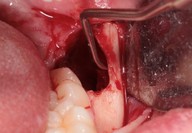

Galleria fotografica